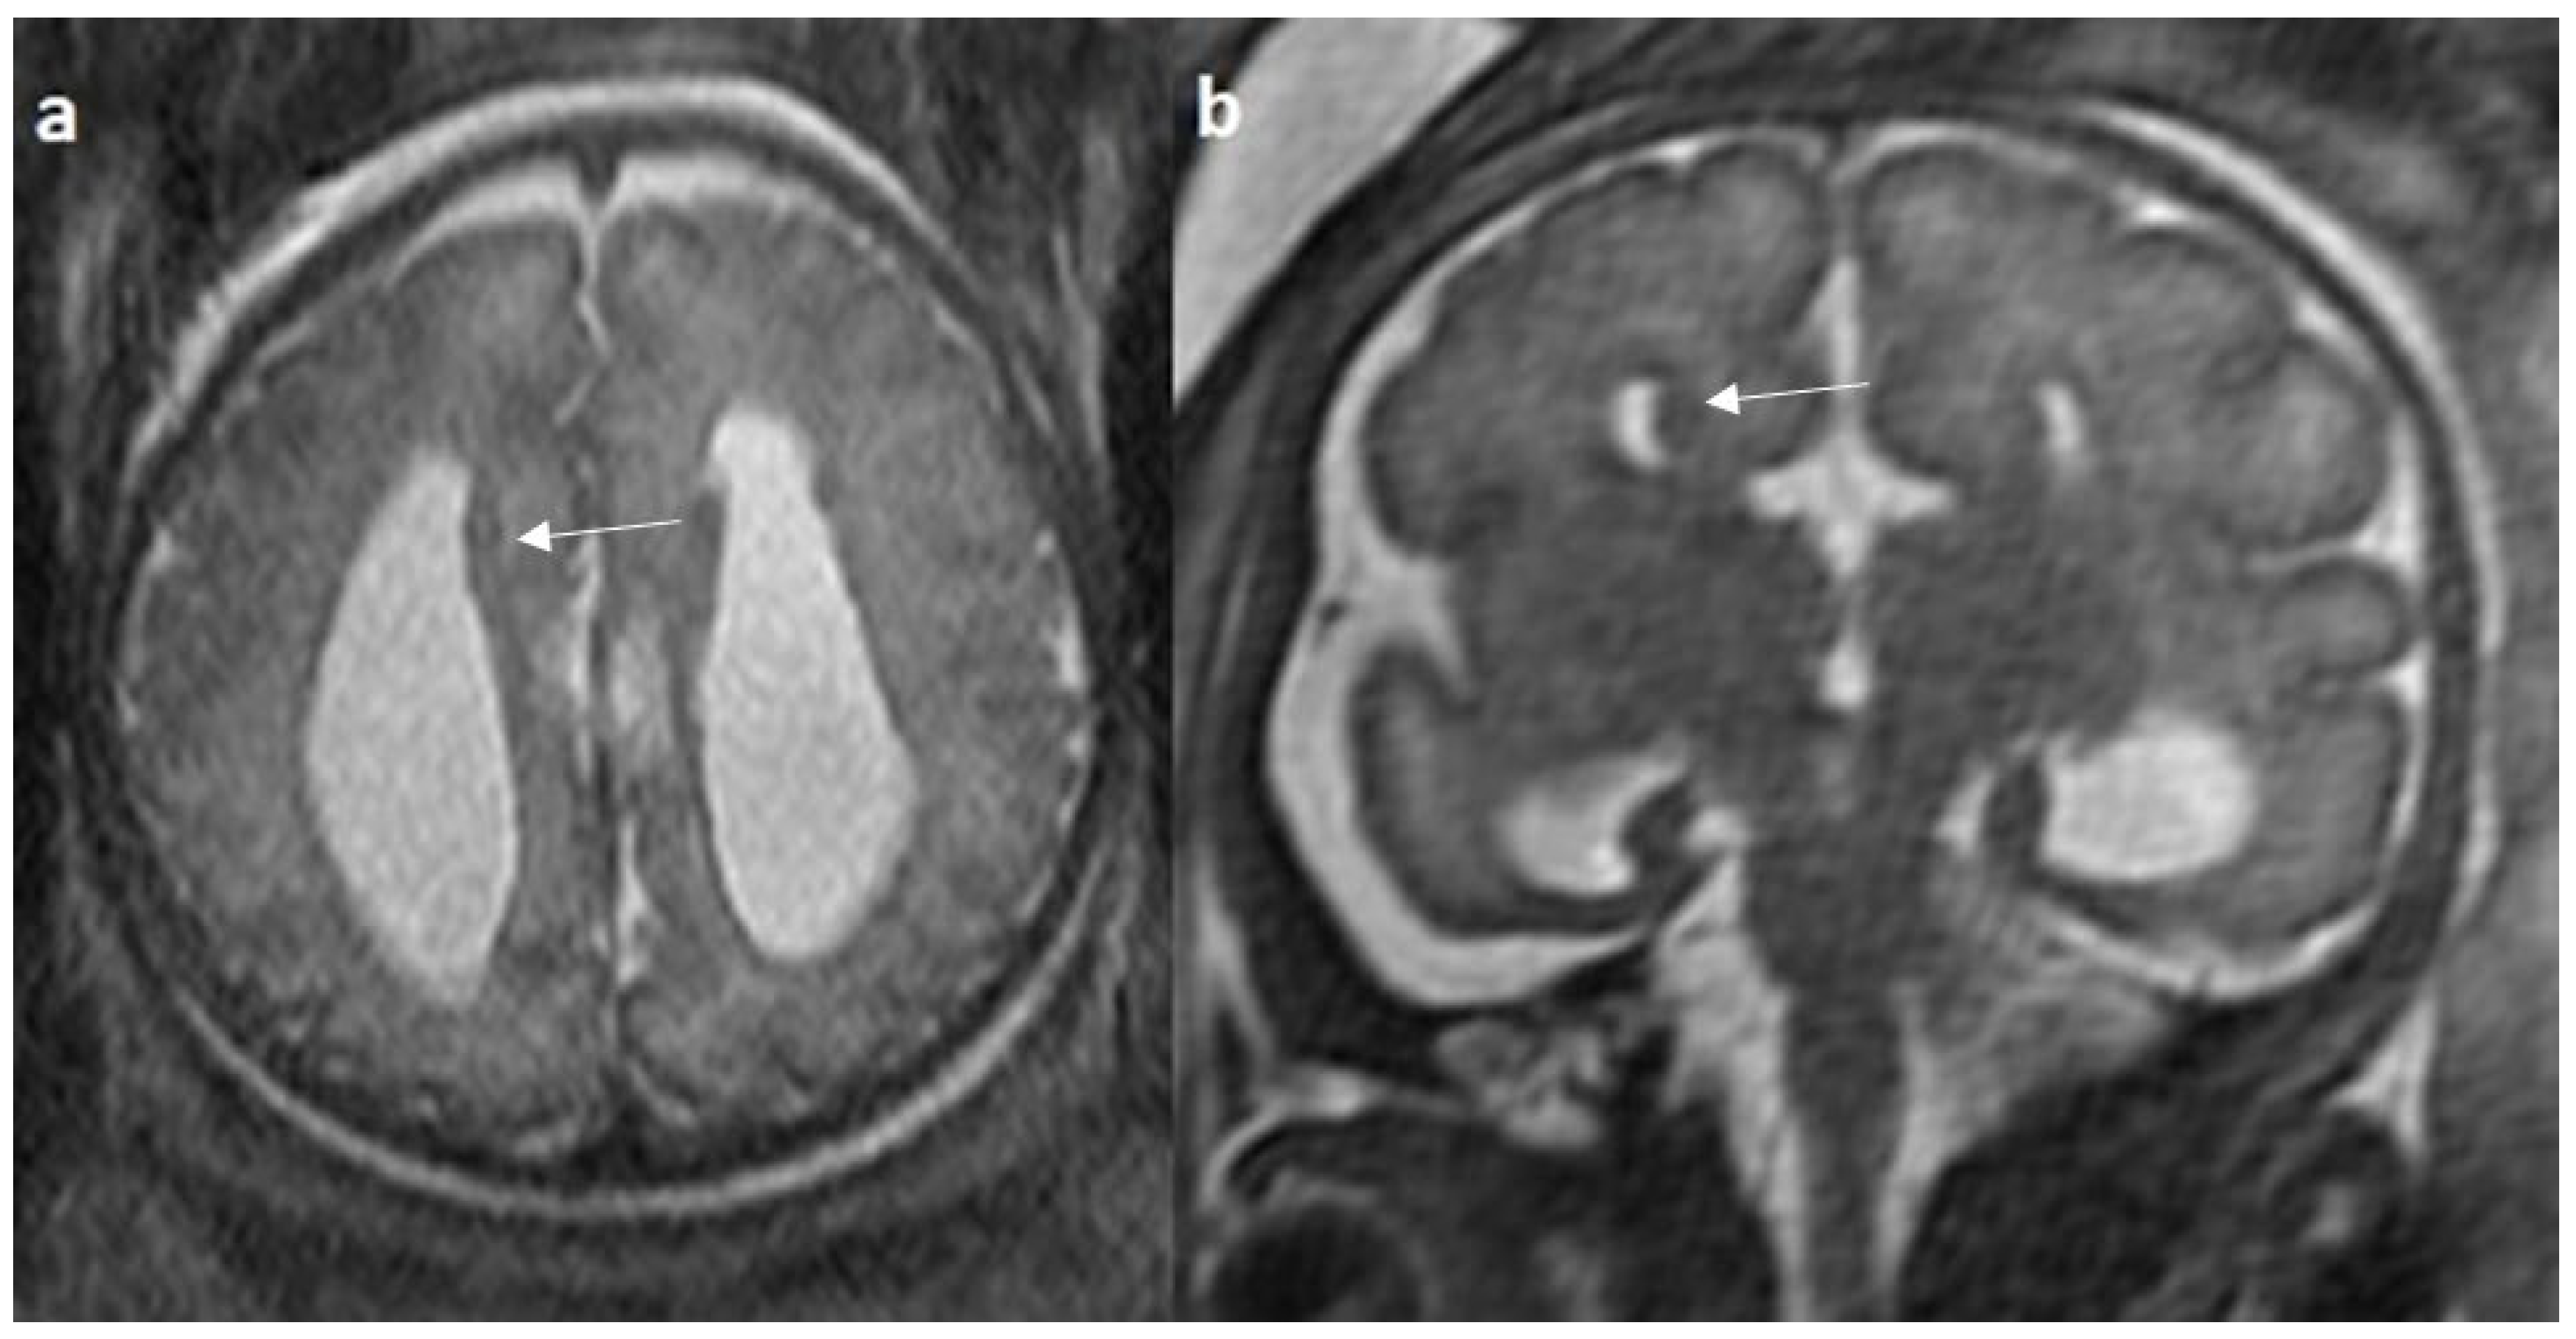

Figure 10.

Fetal MRI images of a 26 gestational weeks aged fetus with hypoplasia of the corpus callosum. (a) A T2-weighted sequence in mid sagittal plane image shows normal anterior part of corpus callosum with absent posterior part (arrow), suggesting hypoplasia of posterior region with anterior remnant, rest of the brain parenchyma in this section is normal. (b) A T2-weighted sequence in axial plane showing a small midline interhemispheric fluid collection/cyst without communication with the lateral ventricles.